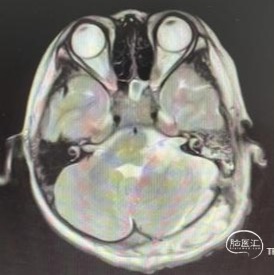

术前CT,MRI

头部CT显示:左侧小半球可见不规则混杂密度影,边界欠佳,其内可见多发钙化,邻近第四脑室受压。双侧脑室稍扩张,骨窗未见异常,左侧内听道未见明显扩大。

头部MRI显示:左侧后颅窝可见一不规则占位性病变,呈等-稍长T1、等-长T2信号,Flare呈稍高信号,大小约67mm*41mm*36mm,病灶突入第四脑室、延髓后方及左侧内听道;脑干及延髓受压变形且向右移位。增强可见不规则不均匀强化。脑室系统稍扩大。